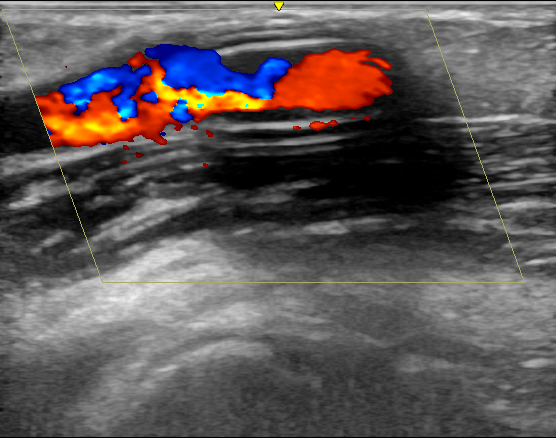

近日 , 西安交通大学第一附属医院肾脏内科透析通路团队为一位人工血管内瘘狭窄的患者成功实施了超声引导下覆膜支架植入术 , 这是陕西省首例在超声下进行的此类手术 , 标志着西安交大一附院透析通路介入治疗技术的又一次提升 。 患者为男性 , 55岁 , 诊断为慢性肾炎 , 慢性肾功能衰竭 , 使用左前臂人工血管内瘘规律透析1年 。 该患者此前因为人工血管内瘘狭窄曾接受两次经皮静脉球囊扩张术(PTA) , 但术后狭窄很快复发 , 对于这种狭窄容易复发且单纯PTA效果不佳的患者 , 覆膜支架植入术是比较好的解决方法 。 经过充分的术前准备和一个小时的手术 , 肾脏内科杨世峰副主任医师及其团队成功为该患者实施了超声引导下覆膜支架植入术 , 术后患者人工血管内瘘血流恢复通畅 , 透析过程中血流量充足、静脉压正常 , 达到了较好的手术效果 。

血液透析通路是尿毒症患者的“生命线” , 目前尿毒症患者最常用的透析通路是自体动静脉内瘘和人工血管内瘘 。 然而内瘘无法避免的并发症就是狭窄 , 长期高速的血流会引起血管内膜反应性增生 , 导致内瘘管腔狭窄和血流量不足 , 影响透析效果 , 狭窄严重时导致内瘘闭塞、血栓和失功 。 处理动静脉内瘘狭窄最有效的方法就是PTA , 通过血管腔内治疗的方法解除狭窄 , 具有创伤小、恢复快的优点 。 然而部分病例单纯PTA后狭窄容易短时间内复发 , 对于这些病例覆膜支架植入是较好的解决办法 。 传统的支架植入术是在DSA造影下进行 , 而超声引导下介入手术是近几年新兴的技术 , 超声引导具有方便、无辐射损伤 , 无造影剂损害、可显示闭塞病变等优点 , 特别适合动静脉内瘘等外周血管的介入治疗 。